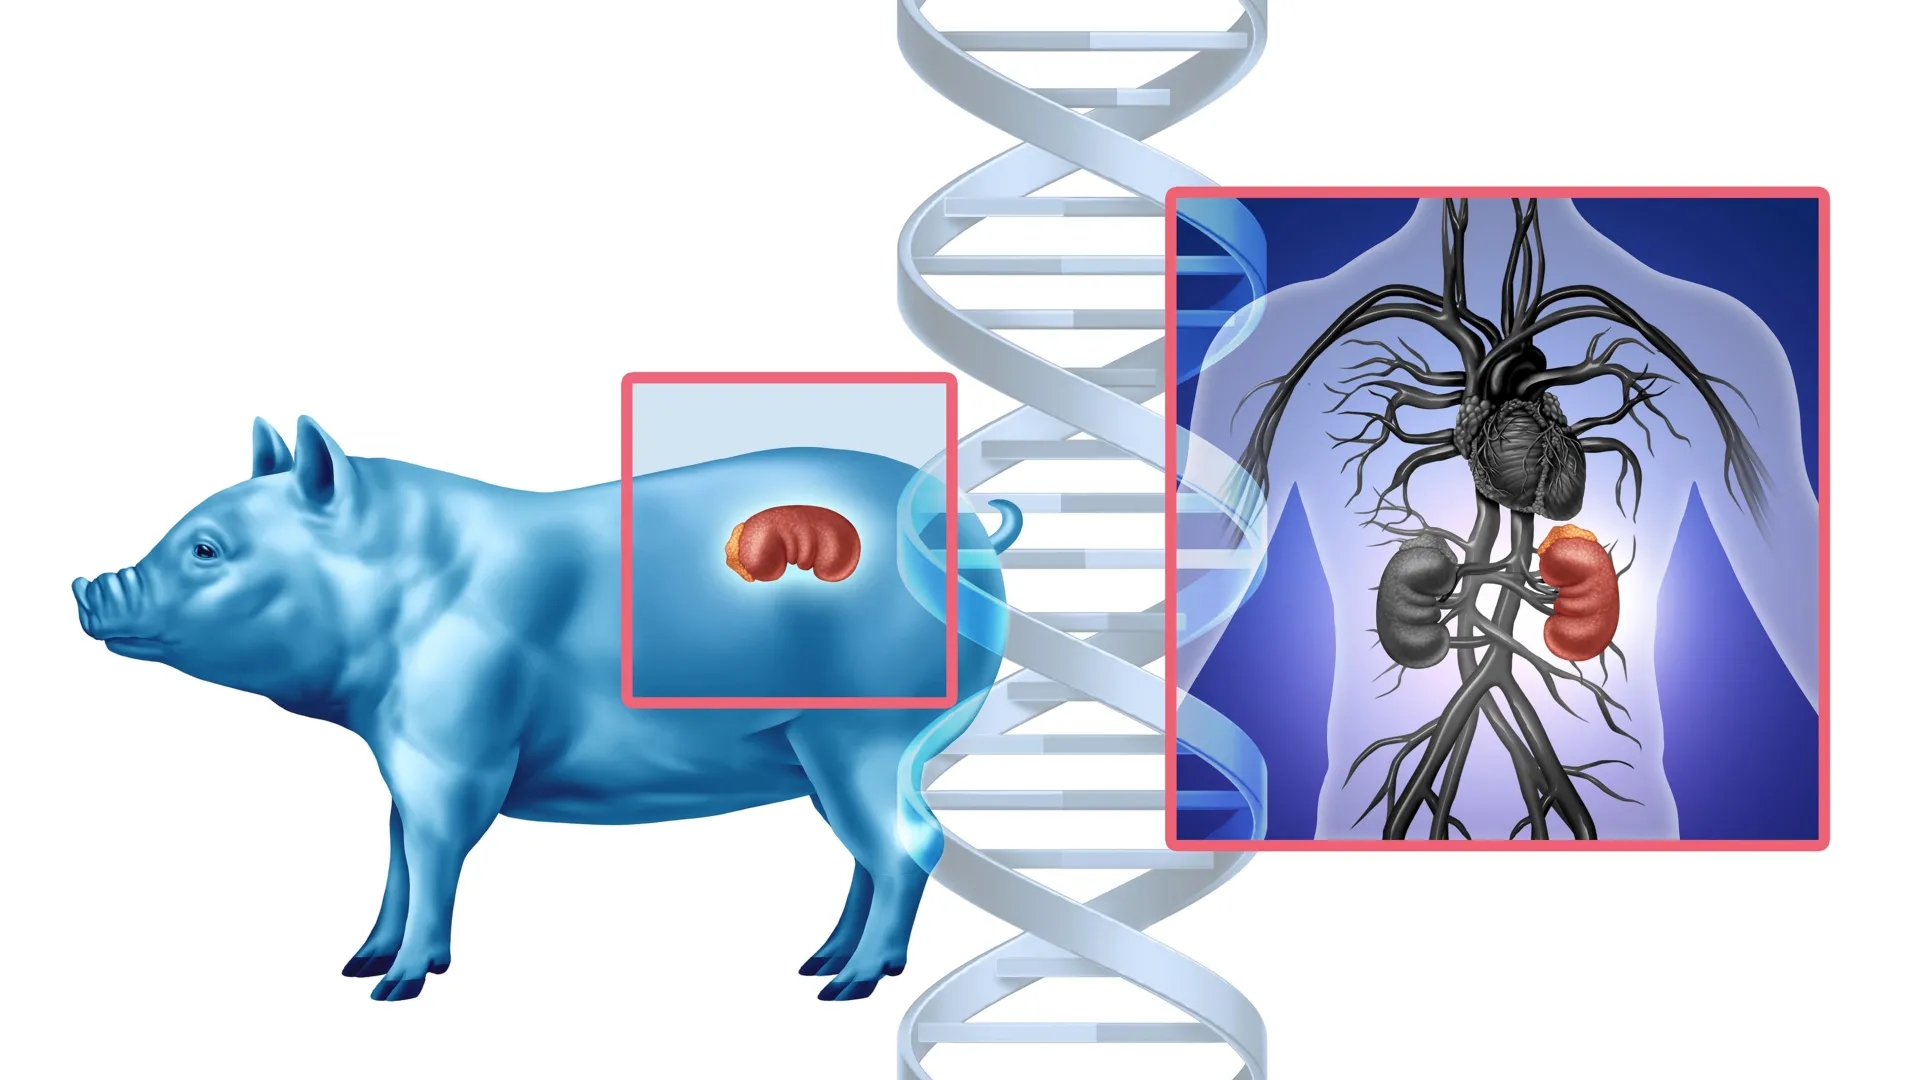

New research from UC Davis Comprehensive Cancer Center has uncovered an evolutionary change that may explain why certain immune cells in humans are less effective at fighting solid tumors compared to non-human primates. This insight could lead to more powerful cancer treatments. The study was published in Nature Communications. It…